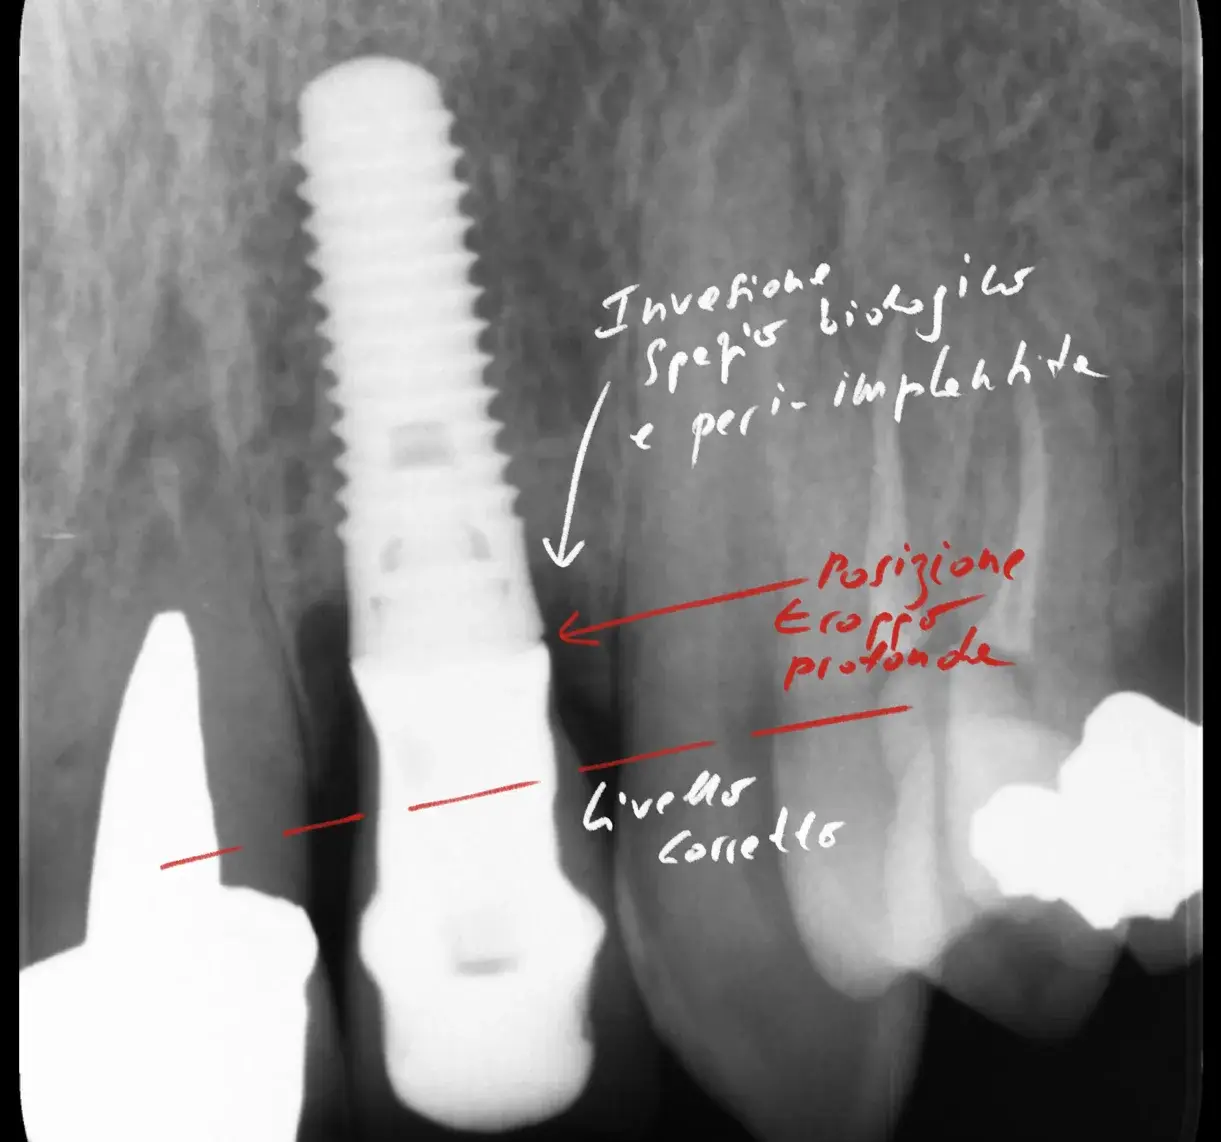

Ma il punto più interessante è un altro. I sette batteri più rilevanti nella parodontite sono gli stessi nella peri-implantite. Stessi nomi, percentuali simili, stessa gerarchia. Sono tutti Gram-negativi.

Questo fatto, da solo, spiega molte cose. Spiega perché i pazienti con storia di parodontite hanno un rischio più alto di peri-implantite. Spiega perché le strategie terapeutiche per le due condizioni tendono a convergere. Spiega perché il mantenimento igienico funziona in entrambi i casi.